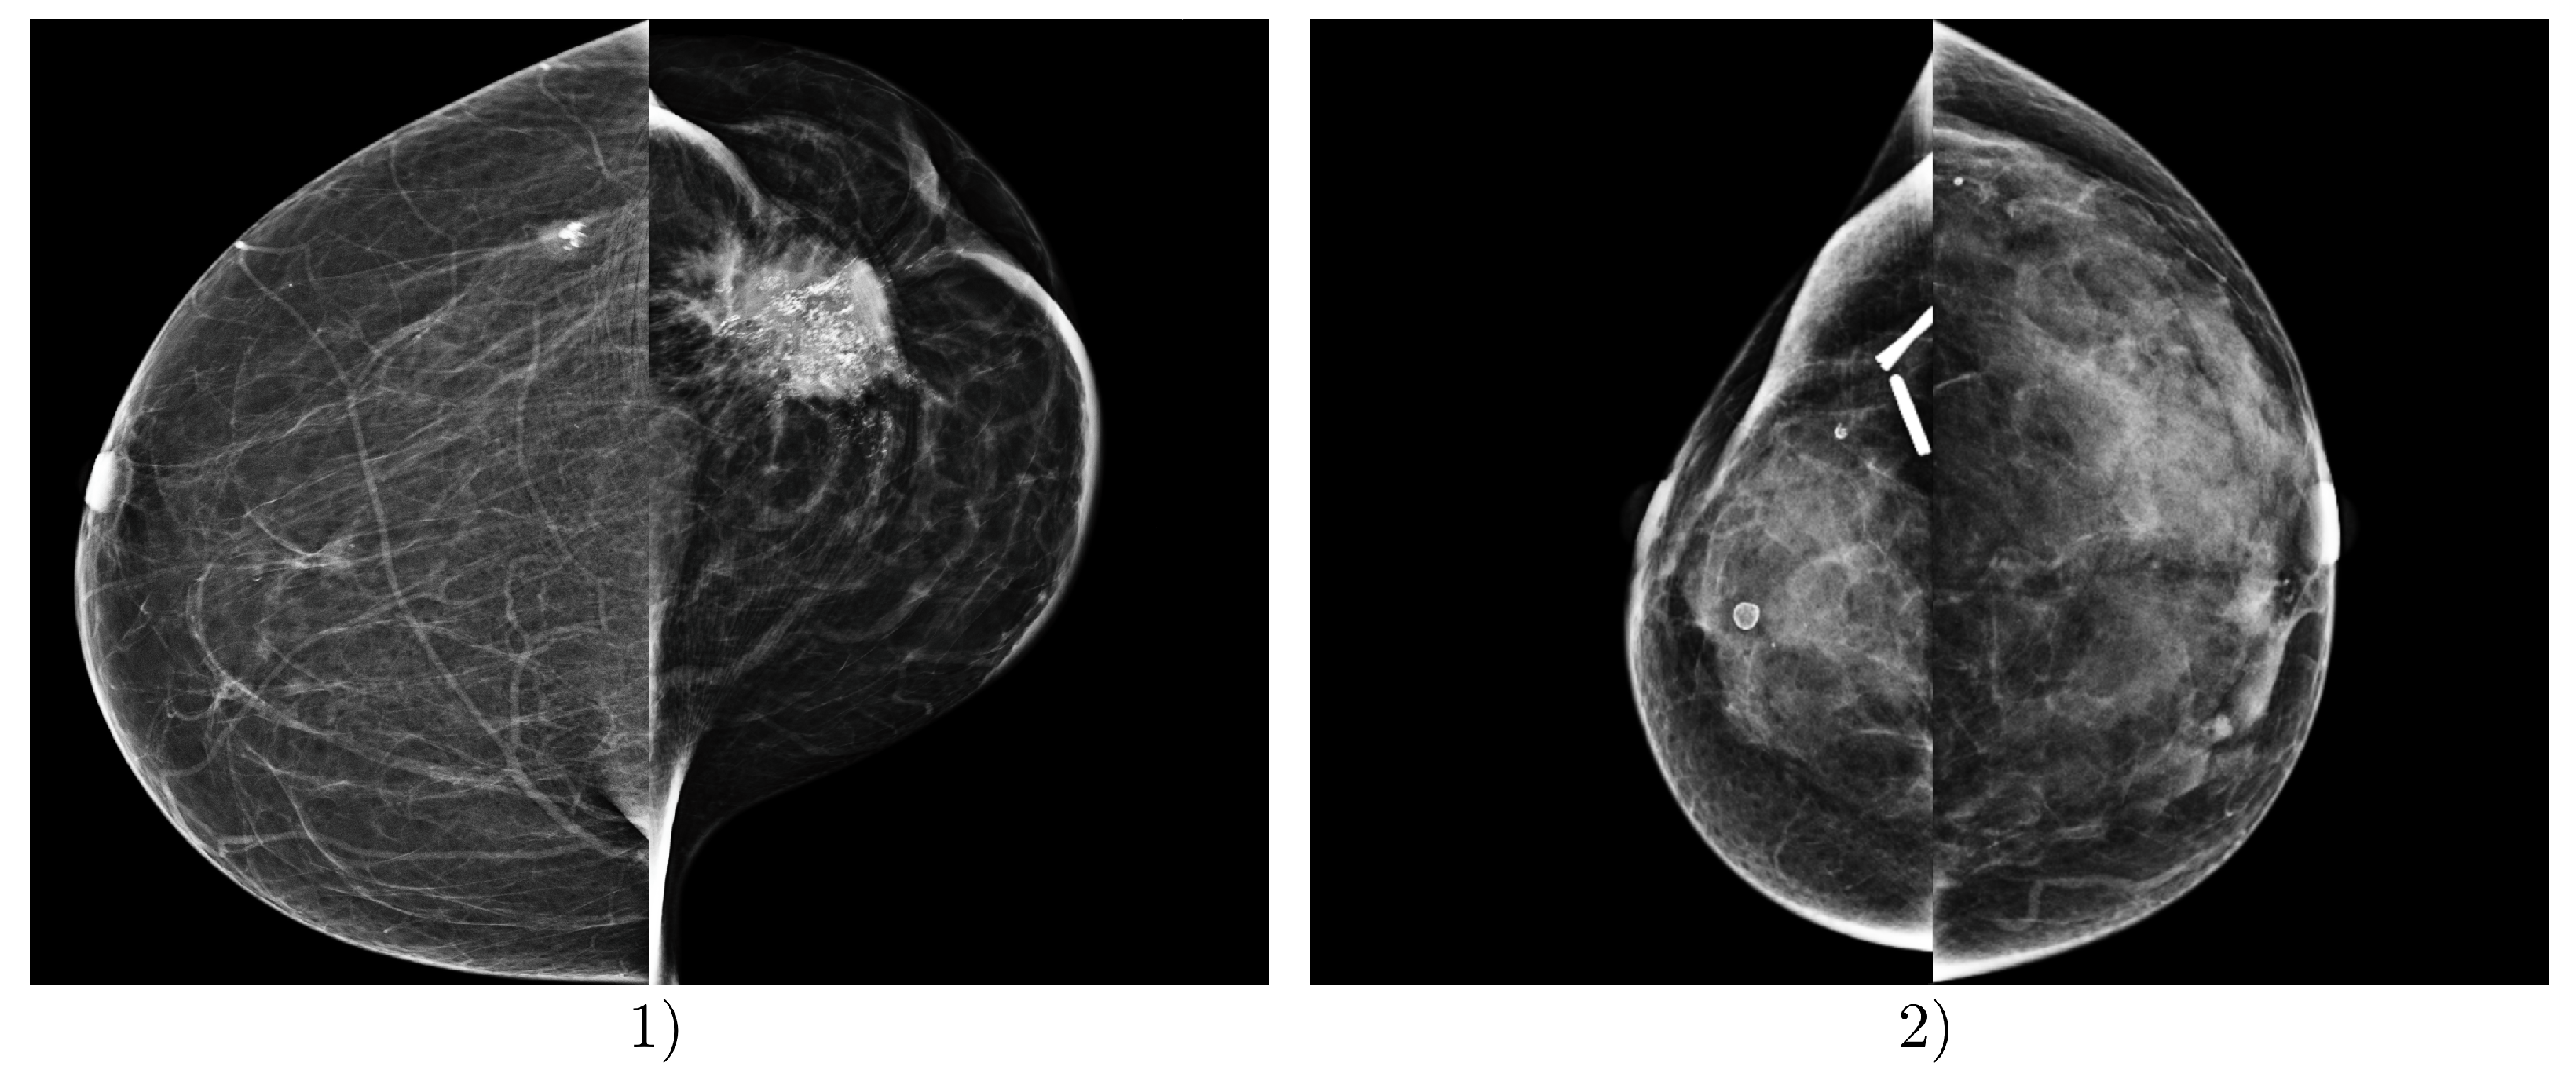

3.1. Software

3.3. Model Architecture

5. Discussion